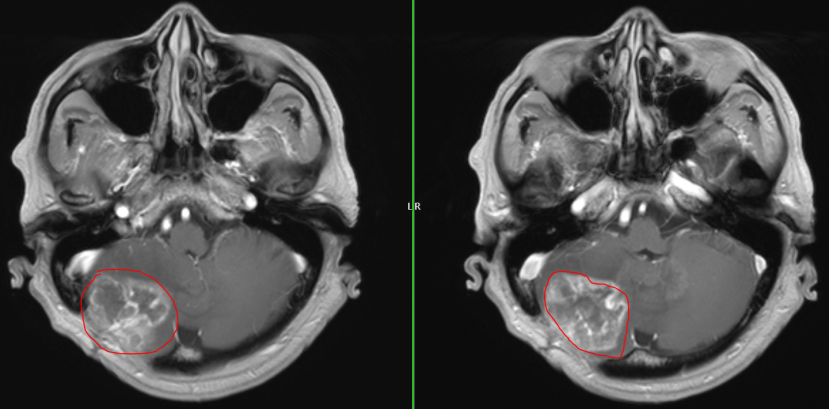

面对如此棘手的局面,周焱峰主任带领团队进行详尽的术前讨论,研读MRI影像,模拟手术入路,为其量身制定手术预案和应急预案。

1e26fa906268e53c2ff8f6b880395fcb.png

术前MRI

32e2d4037feac0a4aa171039b4ce25b6.png

术后MRI

历时4小时,神经外科团队仔细分离粘连组织,准确找到肿瘤边界,完整切除了复发的肿瘤,术中监测平稳,最大程度地保护了神经功能。手术顺利完成,所有人都松了一口气.。